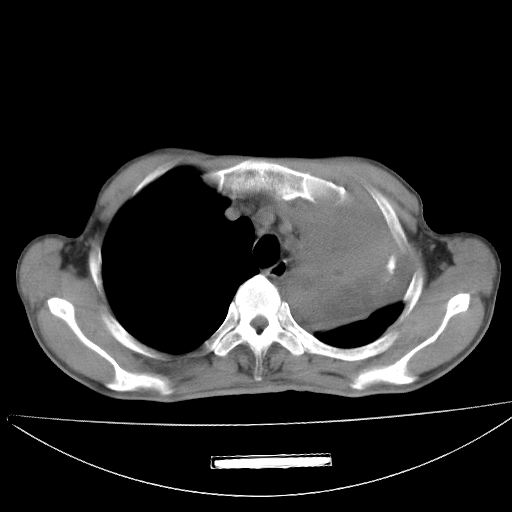

以下是引用杀毒软件在2009-4-28 17:58:00的发言:[br]考虑----左肺慢性肺脓肿形成继发上叶含气不良---抗炎后复查---待排肿瘤所致[br][br][本贴已被 杀毒软件 于 2009-4-28 18:01:26 修改过]